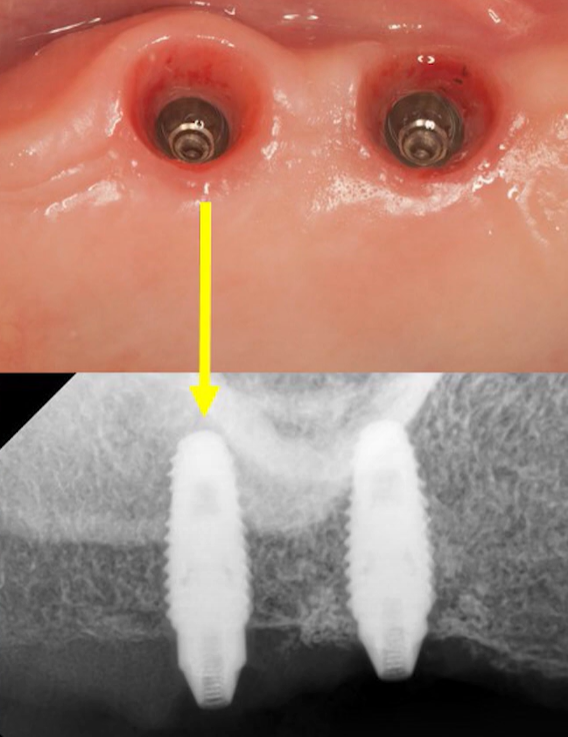

Everything appeared to be perfect: the gingiva was in excellent condition, with no signs of fistulas or inflammation. However, the implant at site #17 spun during the torquing of the multi-unit abutment. The implants at sites #14 and #16 remained stable.

Based on clinical experience and the principles outlined in the study above, the clinician decided not to remove the implant. The multi-unit abutment that caused the failure was left in place, a healing cap was placed over it, and a shortened two-unit bridge was fabricated for the successfully integrated implants. The ability to leave the multi-unit abutment in place was advantageous; if a cement-retained restoration had been planned, attempting to unscrew the abutment would have likely resulted in the complete removal of the implant.

A healing cap was placed over the MUA on the mobile implant, and a shortened bridge was placed on the two stable implants. The compromised implant was left alone for the time required for reosseointegration. Youtube/ Implantarium/ Rauf Aliyev

The patient received the partial restoration and was scheduled for a follow-up in two months to allow for reosseointegration. However, as often happens, the patient returned late, after six months. This was in June 2020.

Radiograph and clinical view after a 6-month break. Youtube/ Implantarium/ Rauf Aliyev

Unfortunately, the clinician did not have an ISQ device at the time, so percussion testing was performed again through the healing cap. The sound was sharp and clear. The implant passed a preliminary test when the clinician removed the multi-unit abutment; the implant remained stable.